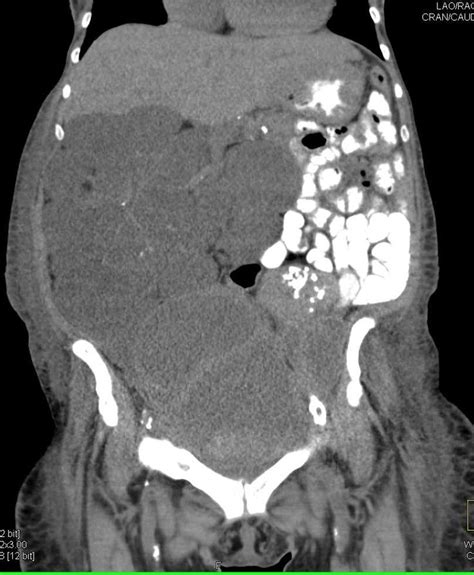

Now, let’s talk about how PMP might show up and how doctors figure out if someone has it. Often, PMP symptoms can be pretty vague, especially in the early stages, which is why it can sometimes take a while to get a diagnosis. Some folks might experience a dull ache or discomfort in their abdomen, and others might notice their belly slowly expanding, maybe their pants feeling tighter. Bloating is another common complaint, and sometimes people might feel a sense of fullness even after eating just a little bit. Changes in bowel habits, like constipation or diarrhea, can also occur, and in some cases, nausea or vomiting might be present. Because these symptoms can overlap with many other, more common conditions like irritable bowel syndrome (IBS) or simple indigestion, it’s easy for PMP to fly under the radar initially. This is where imaging techniques become super important for diagnosis. Doctors will typically start with scans like a CT scan (computed tomography) or an MRI (magnetic resonance imaging) of the abdomen and pelvis. These scans can help visualize the abdominal cavity, identify the presence of tumors, and assess the extent of mucus buildup. The characteristic “jelly-like” substance seen on these scans is a strong indicator of PMP. Sometimes, a colonoscopy might be performed, especially if the appendix is suspected as the origin, to get a closer look at the colon and appendix. However, the definitive diagnosis usually comes from a biopsy. This means a small sample of the tumor or the mucus-filled tissue is taken, either during a diagnostic surgery or a procedure like laparoscopy (a minimally invasive surgery using a small camera), and examined under a microscope by a pathologist. The pathologist looks for specific types of cells and the presence of mucin (the substance that makes up the mucus) to confirm the diagnosis of PMP. It’s a bit of detective work, piecing together the symptoms, imaging results, and pathological findings to get the full picture.